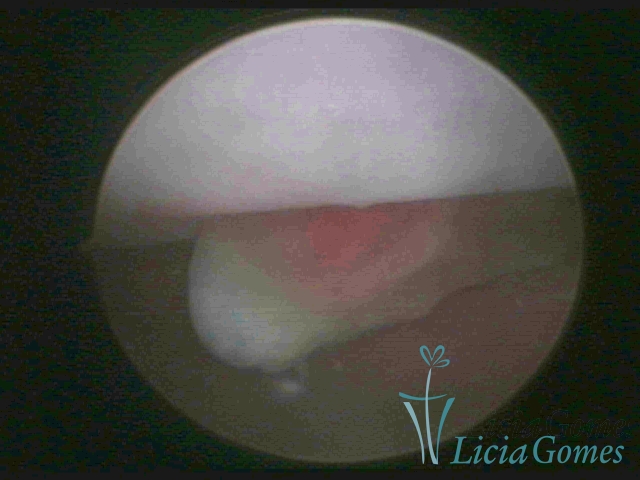

PÓLIPOS ENDOCERVICAIS

São tumores benignos, resultantes da proliferação focal reativa aos processos inflamatórios ou à situações de hiperestrogenismo, e podem ter sésseis (com a base de implantação larga) ou pediculados do epitélio.